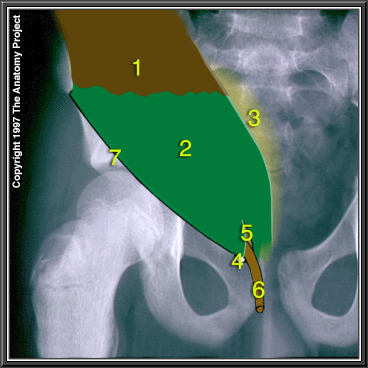

The Coverings of the Inguinal Canal, External Oblique In Situ

Muscular part of external oblique

External oblique aponeurosis

Transversalis fascia

Pubic tubercle

Superficial inguinal ring

External spermatic fascia forming external coating of spermatic cord

Inguinal ligament